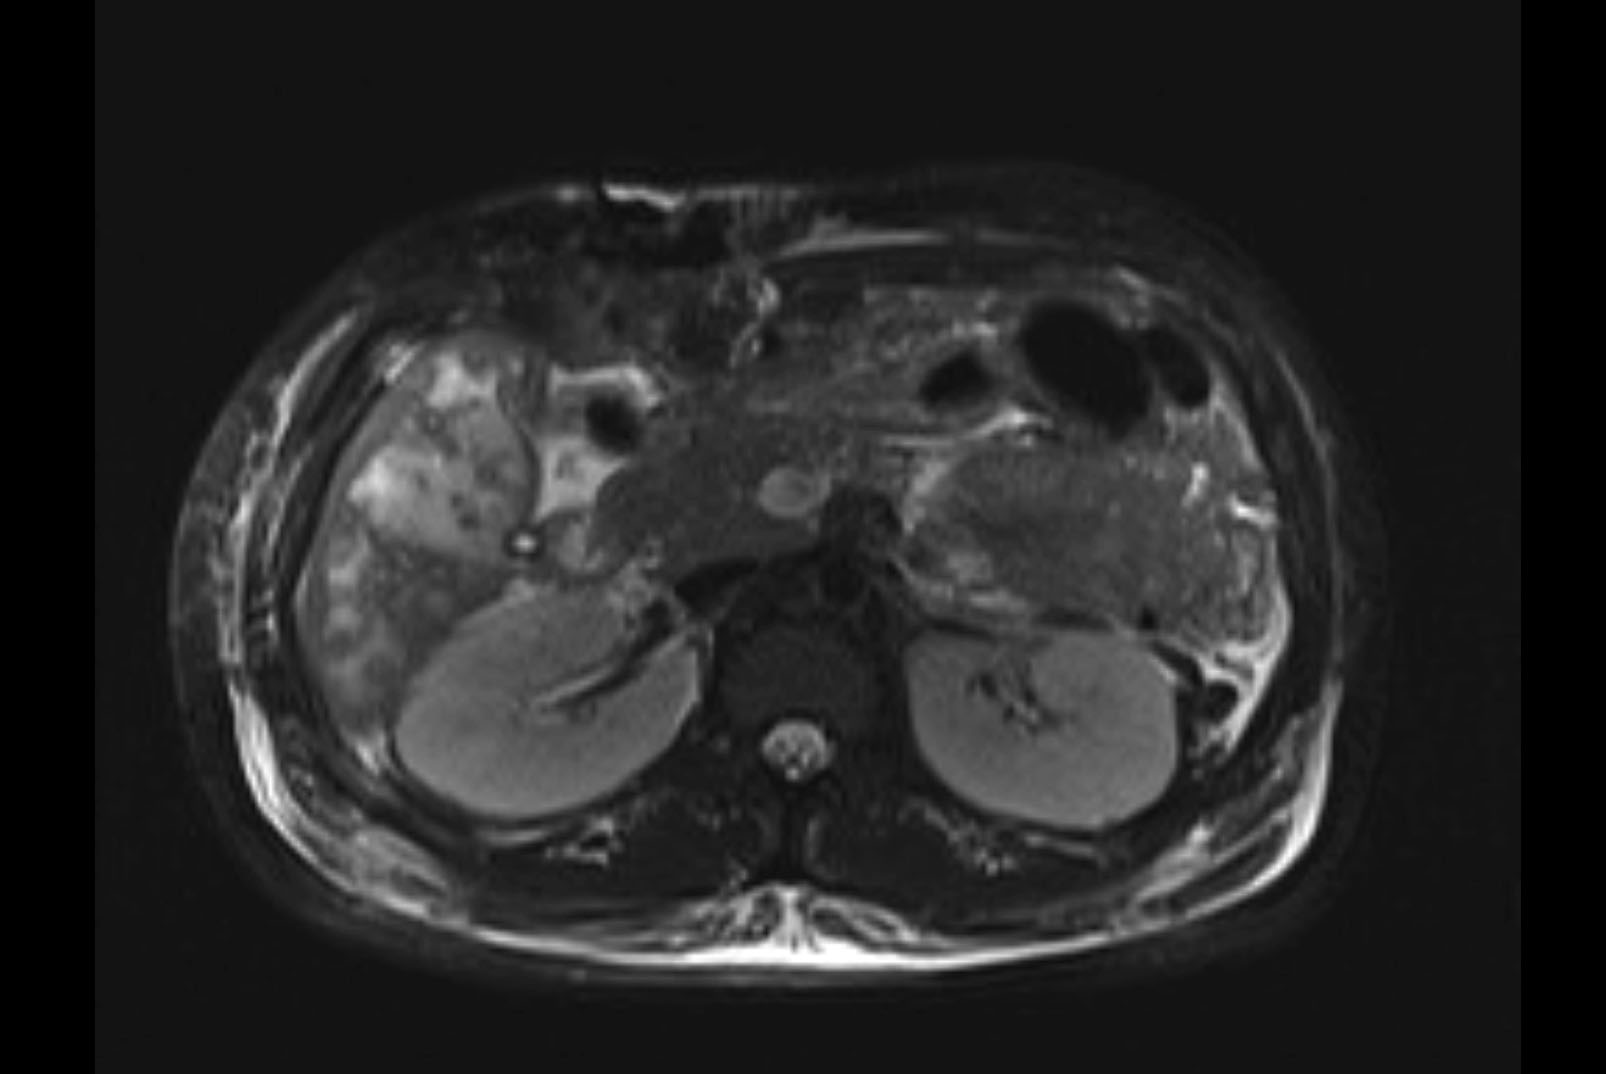

Imaging Analysis

Look through the patient's CT scan to identify any areas of concern for the necessary procedure.

MRI T1

Based on initial findings, which issue(s) would you be most concerned about?